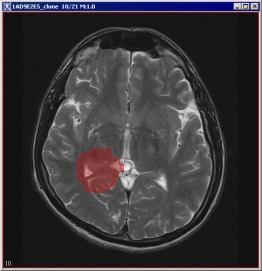

Evaluate Segmentation

Evaluate Segmentation operation compares segmentation results of a test image to segmentation results of an ideal gold standard true image. For each evaluated segmentation pair, the false negative volume fraction, the false positive volume fraction, and the positive volume fraction are sent to the Output window. See Figure 13)-e.

Figure 13. The Evaluate Segmentation algorithm : (a) - a gold standard segmented image, (b) - its unsigned byte mask, (c) - a segmented image for evaluation, (d) - its unsigned byte mask, and (d) - the Evaluate Segmentation dialog box and the Output window